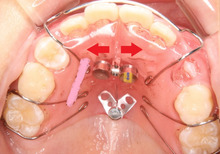

下の写真の矢印の部分の隙間に

大きな犬歯が生えなければいけません。

お母さんの心配通り、隙間はありません。

このままだと 八重歯になります。

まだ骨は軟らかい、小学生なので、

骨を広げる装置を入れます。

この装置は拡大床(かくだいしょう)

といいます。